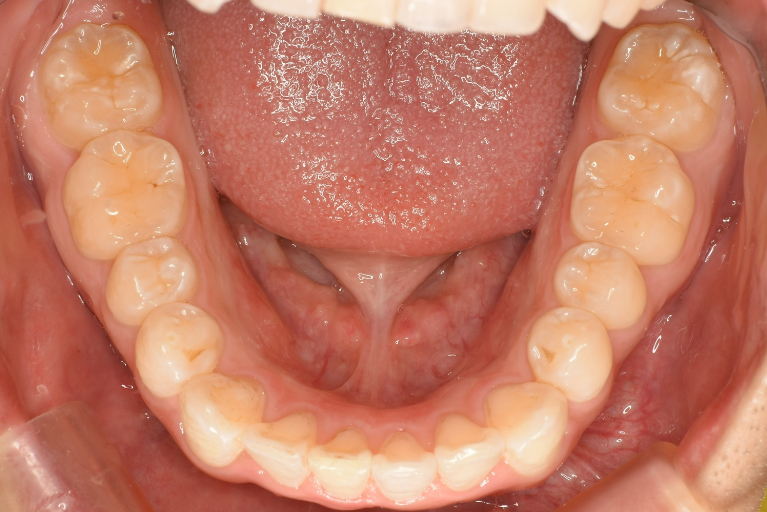

術前

術中

術後

| 治療名 | インビザライン・ライトによる前歯のガタつき改善症例 |

| 治療説明 | 前歯のガタつき(叢生)をマウスピース型矯正装置「インビザライン・ライト」で改善した症例です。 全体的な咬み合わせには大きな問題がなかったため、短期間で前歯の並びを整えることができました。ワイヤーを使わず、透明なマウスピースで目立たずに治療を行いました。 |

| 治療回数・期間 | 約4ヶ月 |

| 副作用とリスク | ・インビザライン矯正では、1日20時間以上のマウスピース装着が必要です。 ・歯の移動に伴って、痛みや咬合時の違和感が生じることがあります。 ・歯ぐきが下がる(歯肉退縮)や、歯の根が短くなる(歯根吸収)などの可能性があります。 ・使用できるマウスピースの枚数に制限があるため、すべての症例に適応できるわけではありません。 |

| 料金(税込) | 770,000円 |